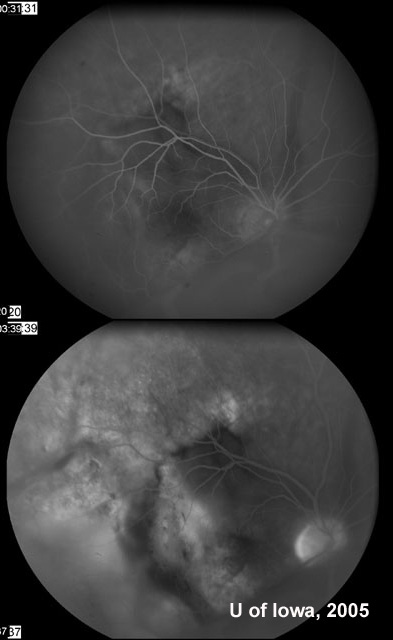

荧光素血管造影术结果见图3

图3:右眼血管荧光照影图。注意后来被染色的大面积区域实际大于苍白区域本身。